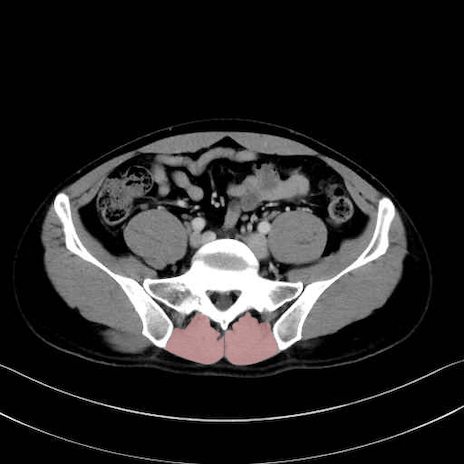

肛門挙筋 (Levator ani)